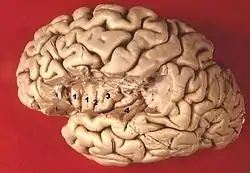

Section of brain showing upper surface of temporal lobe ("transverse temporal gyri" visible at center left)

Human brain view on transverse temporal and insular gyri (gyri temporales transversi are #4)